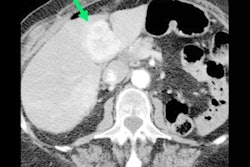

The typical indications for 4D CT, MRI, PET/CT are preoperative localization in indeterminate cases, evaluation of multi-gland disease, persistent/recurrent PHPT following initial surgery, and evaluation of small adenomas.

"Imaging guidelines vary, but all suggest preoperative localization imaging if minimally invasive parathyroidectomy is to be considered, or prior to repeat surgery," the authors noted. "Concordance between two (or more) modalities is often preferred, particularly in cases of persistent/recurrent PHPT."

For F-18 fluorocholine PET/CT, the typical appearance is increased tracer uptake relating to a well-circumscribed nodule adjacent to the thyroid, or within the neck or upper mediastinum. Optimizing the PET window settings may help to identify the most accurate focus and thus improve detection of small lesions on the CT component, the Imperial team recommended.